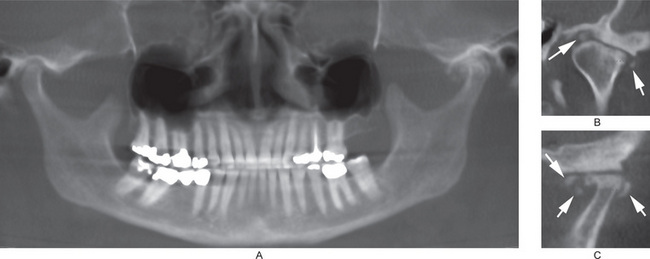

Ankylosis of the TMJ is a disorder in which adhesion of joint components takes place by fibrous or bony union, resulting into loss of function (Fig. 17-38).

Figure 17-38 Ankylosis of the temporomandibular joint.

The images are tomography of the left temporomandibular joint in the closed and open mouth positions. A radiopaque band of tissues extends from the condylar head to the anterior slope of the articular fossa. On the open mouth view, the condylar head barely translated.

About 17–52% mandibular fractures involve condylar fracture. Zachariades et al have provided a thorough review of condylar fractures. Condylar fractures may be classified according to the anatomic location, e.g. the condylar head (intracapsular), the condylar neck (extracapsular) and the subcondylar region. Condylar fractures may also be classified as nondisplaced, deviated, displaced (medial or lateral), and dislocated (Fig. 17-42). Another classification is according to the orientation of the fracture line, e.g. horizontal, vertical or compression type. Condylar fracture results from an acute traumatic injury to the jaw and is accompanied by limitation of motion and pain and swelling over the involved condyle. The fractured condyle fragment is frequently displaced anteriorly and medially into the infratemporal region because of the forward pull of the external pterygoid muscle, and reduction of the fracture is often difficult because of this displacement. In unilateral fracture of the condyle, the body of the contralateral mandible is also likely to fracture. In fatal automobile accidents, a fracture condyle may be dislocated into the cranium. Open reduction of the fracture fragments is indicated in case of limited range of motion or loss of function. Surgical reduction of the fracture fragments may not be necessary if the patient has adequate function.

Figure 17-42 Fracture of the condylar temporomandibular joints.

(A, B, and C) From the same patient’s cone beam computed tomography scan. Both the condylar heads are vertically fractured. The reconstructed panoramic view (B) shows the fractured fragments of the condylar heads are dislocated anteriorly. (D, E, and F) From the same patient’s cone beam computed tomography scan. D, Shows a hairline fracture (arrow) of the right condylar head. Figure E shows fractured and anteriorly displaced left condylar head. Both the maxillary sinuses are cloudy. F, shows fractured left condyle, and that fracture fragment is displaced to the peak of the articular eminence. (G) Fracture of the left side at the condylar neck region. Open mouth Towne’s radiograph shows the fractured fragment (arrows) is medially inclined. (H) Fracture of the right side at the condylar neck region. Open mouth Towne’s radiograph shows the fractured fragment (arrows) is displaced medially and is horizontally oriented.